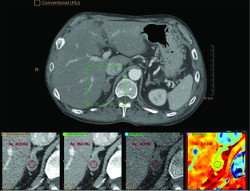

Patient, who was previously diagnosed with hepatic cell carcinoma and liver cirrhosis, underwent ablation to treat the hepatic lesions. Ablation effectiveness following treatment was a concern. The following images were taken on the Philips IQon Spectral CT. The conventional CT image shows what could be a suspicious area in the liver. However, further enhancement was needed to better visualize the possible lesion. Normally, this patient would require additional scanning, such as MR or ultrasound.

Spectral Monoenergetic (MonoE) Image This 45 keV MonoE image reveals visualization of a suspected lesion. An additional scan is not needed to confirm.

Z Effective Spectral Results In the Z Effective spectral image, you can visualize iodine uptake, adding another layer of information. Because spectral information is always on with the IQon Spectral CT, this additional information is available whenever a deeper analysis is needed.